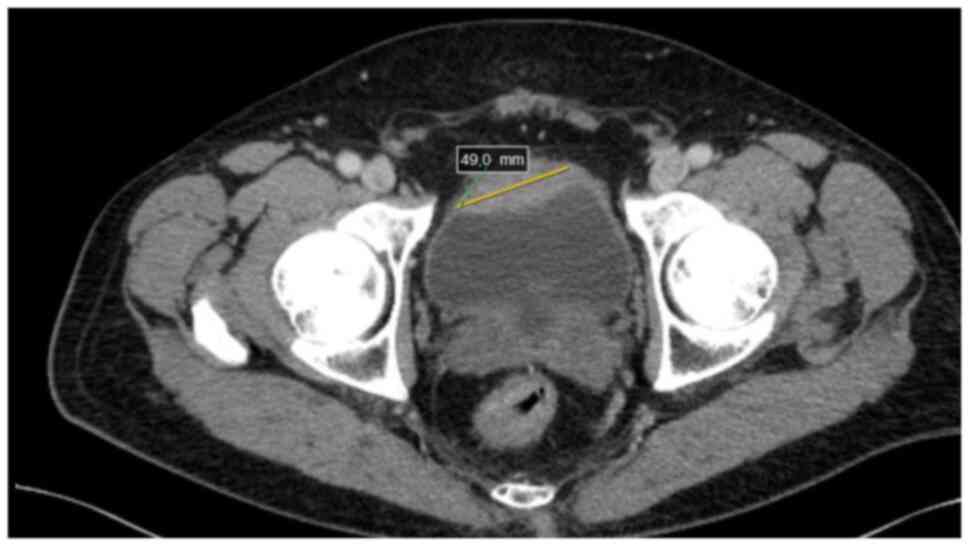

A 67-year-old male patient with a history of hypercholesterolemia, and no other comorbidities, was referred to the urologist for hematuria in September 2021. The patient underwent transurethral resection of the bladder tumor and was diagnosed with pT2 high-grade urothelial bladder cancer. The patient was then referred to the Department of Urogenital Cancer at the Maria Skłodowska-Curie National Research Institute of Oncology (Warsaw, Poland). Computed tomography (CT) performed in October 2021 due to the diagnosis of muscle-invasive bladder cancer detected a neoplastic infiltration of the anterior wall of the urinary bladder, measuring ~13×49 mm, extending beyond the bladder wall, with no lymphadenopathy or metastatic changes in parenchymal organs or bones (Fig. 1). The patient received neoadjuvant treatment consisting of four courses of gemcitabine and cisplatin chemotherapy, followed by a cystoprostatectomy in March 2022. During the cystoprostatectomy, the Bricker technique of urinary diversion was used, which involves spatulating the ends of the ureters and suturing each ureter separately to the end of an isolated intestinal loop, the so-called Bricker loop, the other end of which is used as a urostomy (5). There were no clinical or intraoperative indications for additional removal of the appendix; therefore, the appendix was left in place.

Figure 1.

Preoperative CT scan. Neoplastic infiltration of the anterior wall of the urinary bladder, measuring ~49 mm in its greatest dimension, marked with a yellow bar.